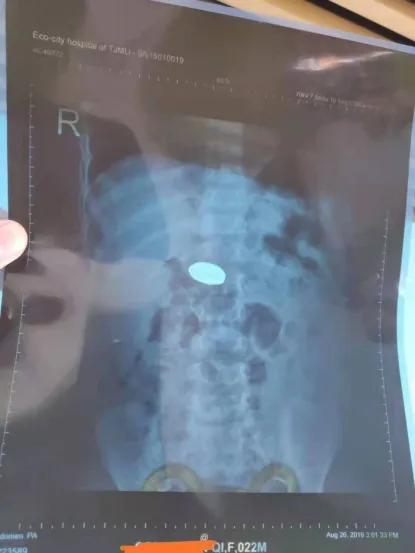

如下图病历是我院查到的 异物卡顿与胃底处,之后3天未排出消化道(排大便中未见异物出现),最终转天津市儿童医院行胃镜诊治的病例,而取出异物就是之前吞入的钢镚,但嵌顿于胃窦处时间较长,已经引发出血性胃炎。